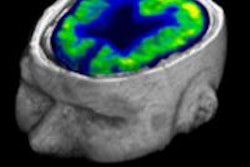

In another PET study, researchers from Europe used FDG-PET to predict which patients with severe brain injuries might regain consciousness. That story is available by clicking here, or visit our Molecular Imaging Community at molecular.auntminnie.com.

MRI of schizophrenia

Finally, be sure to check out our MRI Community for a new study that sheds light on schizophrenia and the brain. Researchers using MRI discovered that the brains of individuals with the disorder actually have the capability to reorganize and fight the disease. Learn more by clicking here, or go to the MRI Community at mri.auntminnie.com.